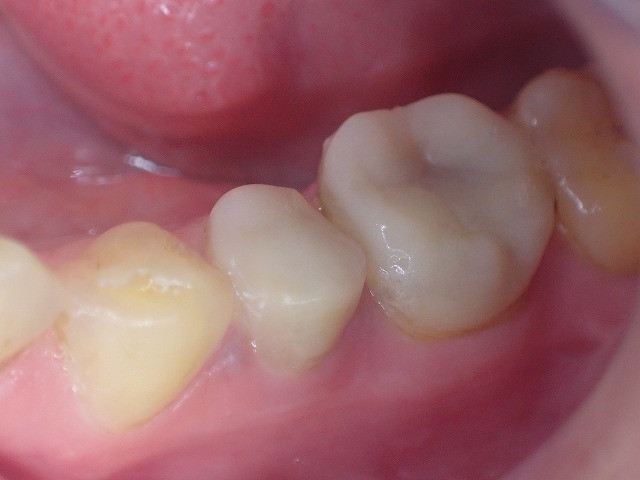

左下

プラスチック冠 おそらくcad/cam冠

かもしれません。

歯と歯はお互いに接触しなくてはなりません。

「コンタクト」と言って歯科では重要視される

状態で、適切なコンタクトが歯周病や虫歯、

咬み合わせなどに関与しています。